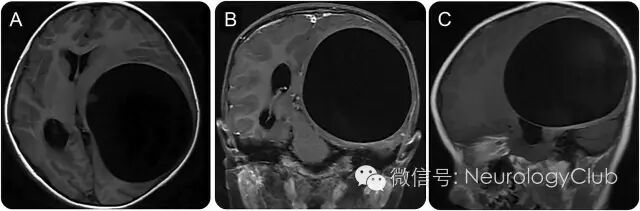

6岁女孩,表现为进行性左眼斜视和视力下降3月。头颅MRI提示左侧大脑半球单发低信号病灶,无灶周水肿或对比强化(图1,A-C)。

(图1:A:T1WI;B:T1增强;C:T1WI;可见单独的左侧大脑半球低信号病灶,无灶周水肿或对比增强)